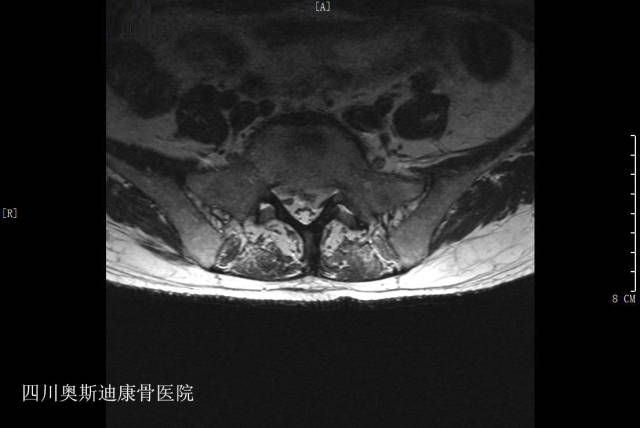

影像学所见:L4-5、L5-S1椎间盘膨出、突出(中央型),椎管狭窄;腰椎退变,L3-S1椎间盘变性,L5-S1椎间盘及终板改变考虑退变可能,不除外椎间盘终板炎;腰骶部软组织水肿;L1椎体陈旧压缩骨折。

诊断:L5-S1椎间盘炎、L4-S1椎间盘突出症